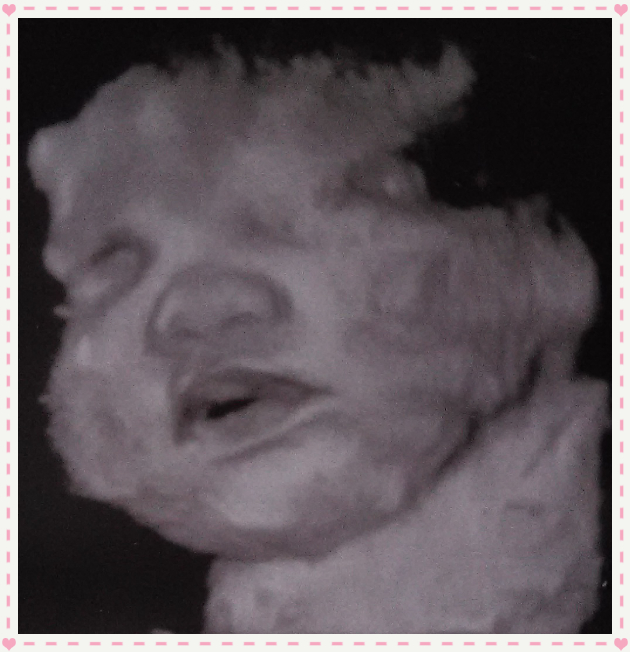

PS the pictures are from my ultrasound at 36wks (had a wonderful tech who gave us these 4d pics) just wanted to show off my chubby little monkey. DH & I just can't wait to finally meet her and have been praying non-stop that everything works out OK.